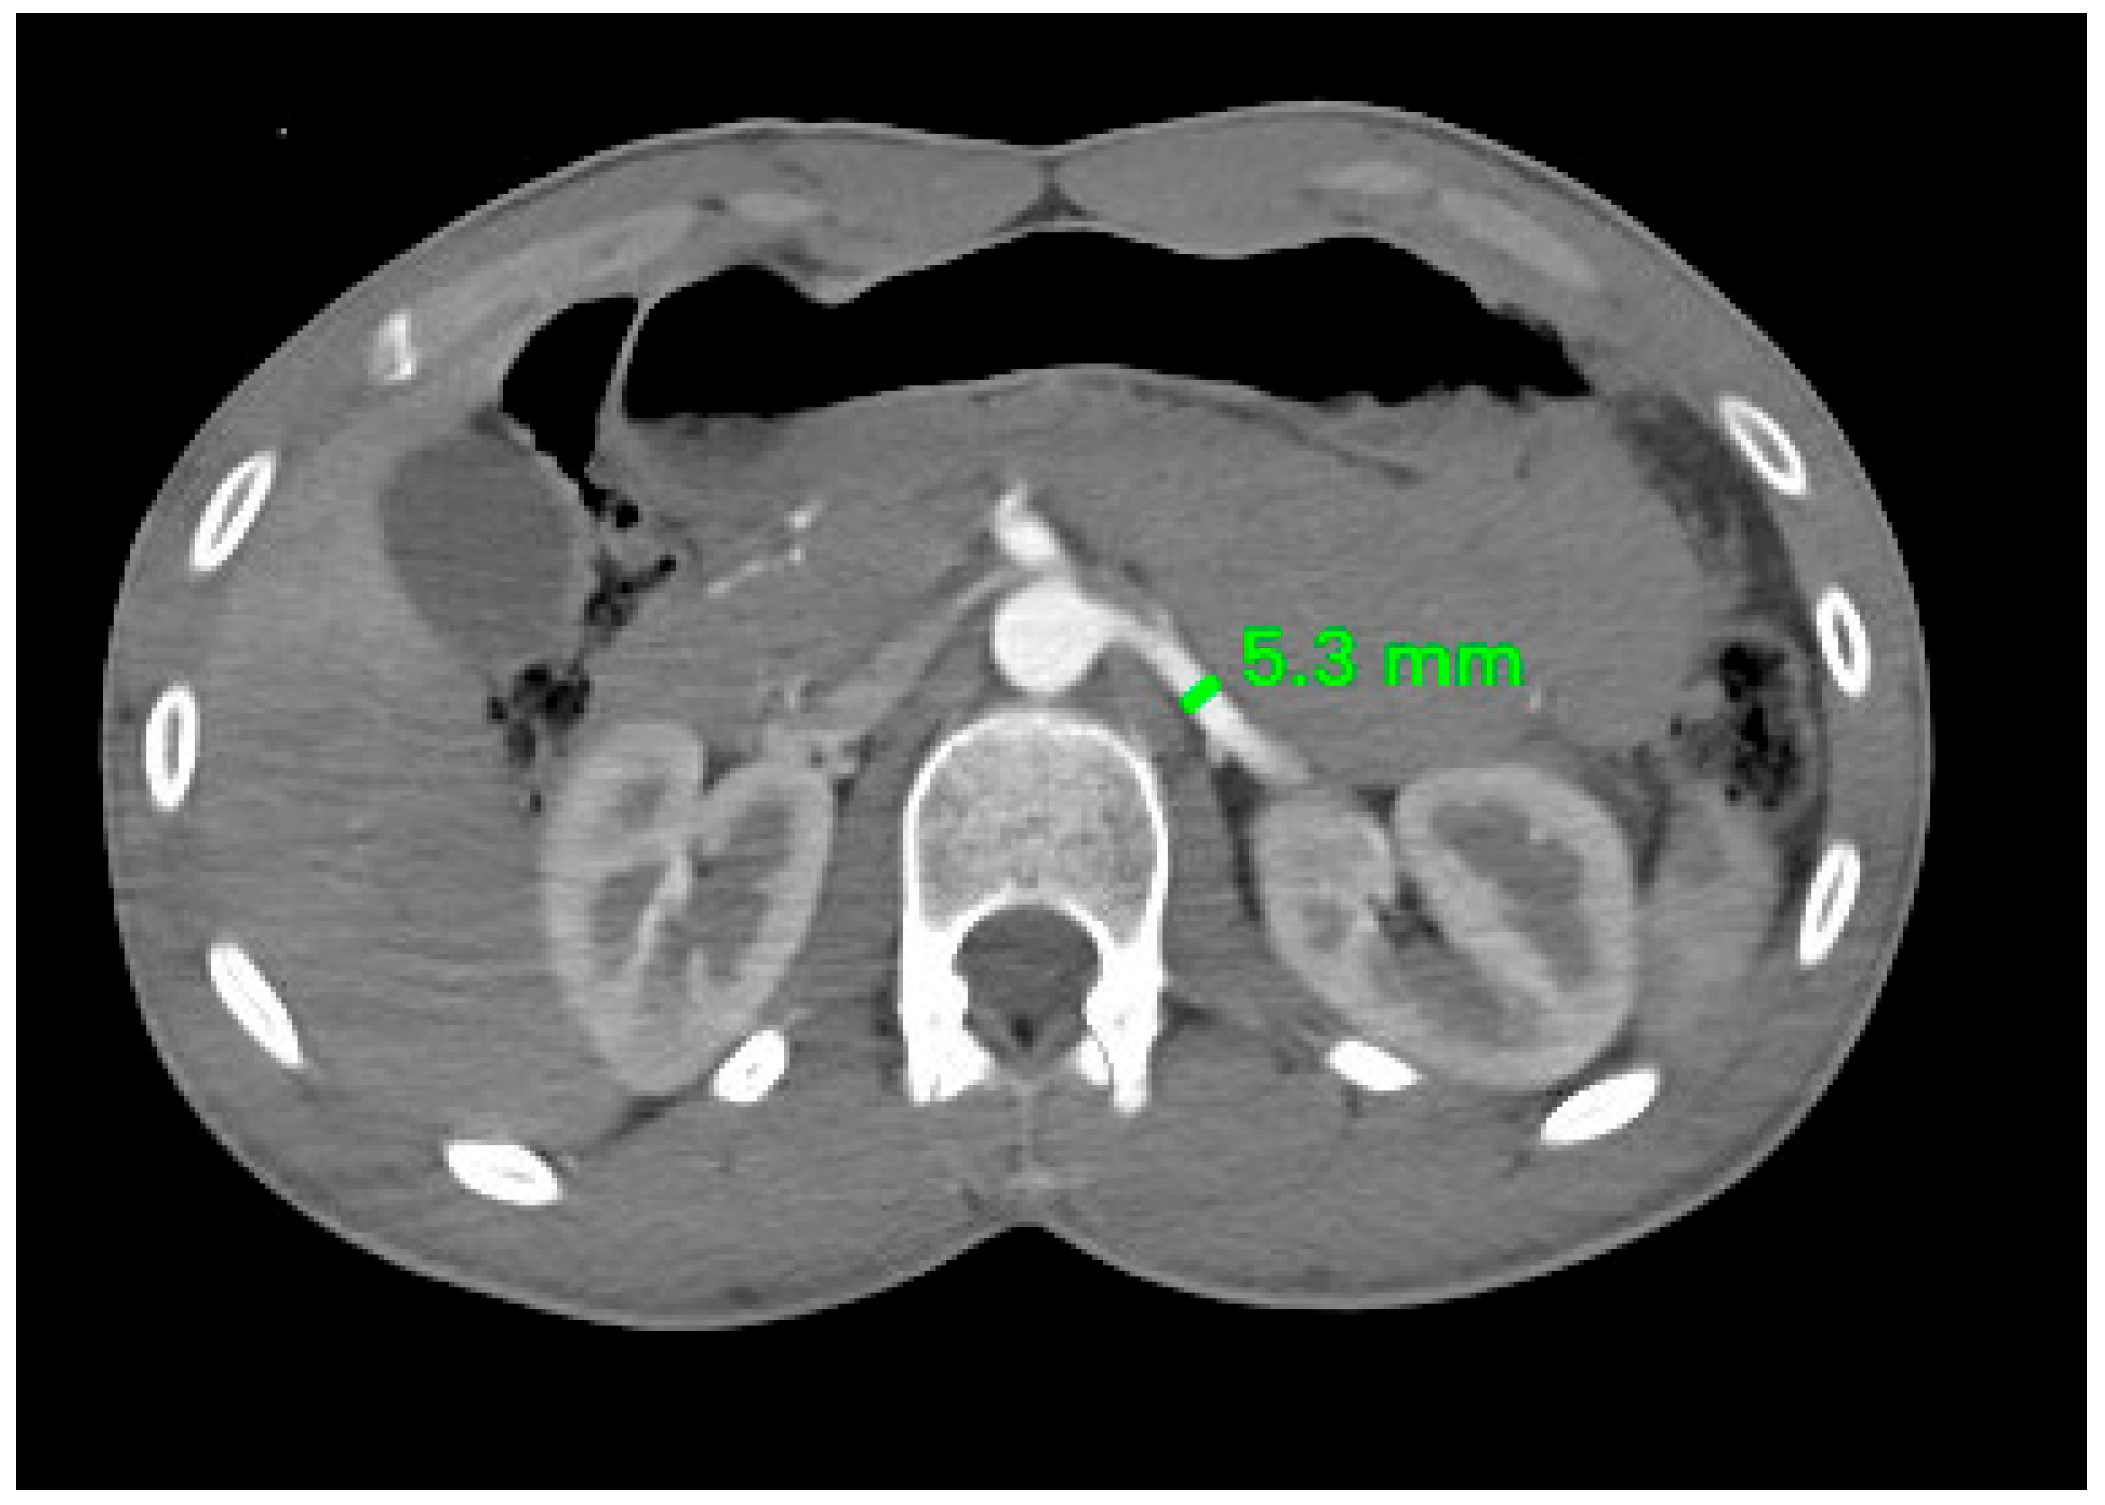

| Left RA | 5.07 ± 1.04 mm | 4.64 ± 0.76 mm | 0.026 |

| Muscat, Oman (our study) | 2025 | 128 (92M, 36F) | 4.62 mm (M), 4.22 mm (F) | 5.07 mm (M), 4.64 mm (F) | This study |